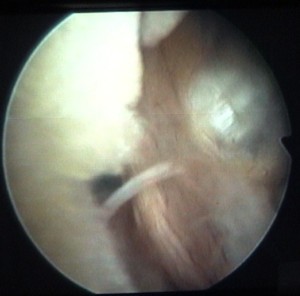

enlèvement d'un ménisque |